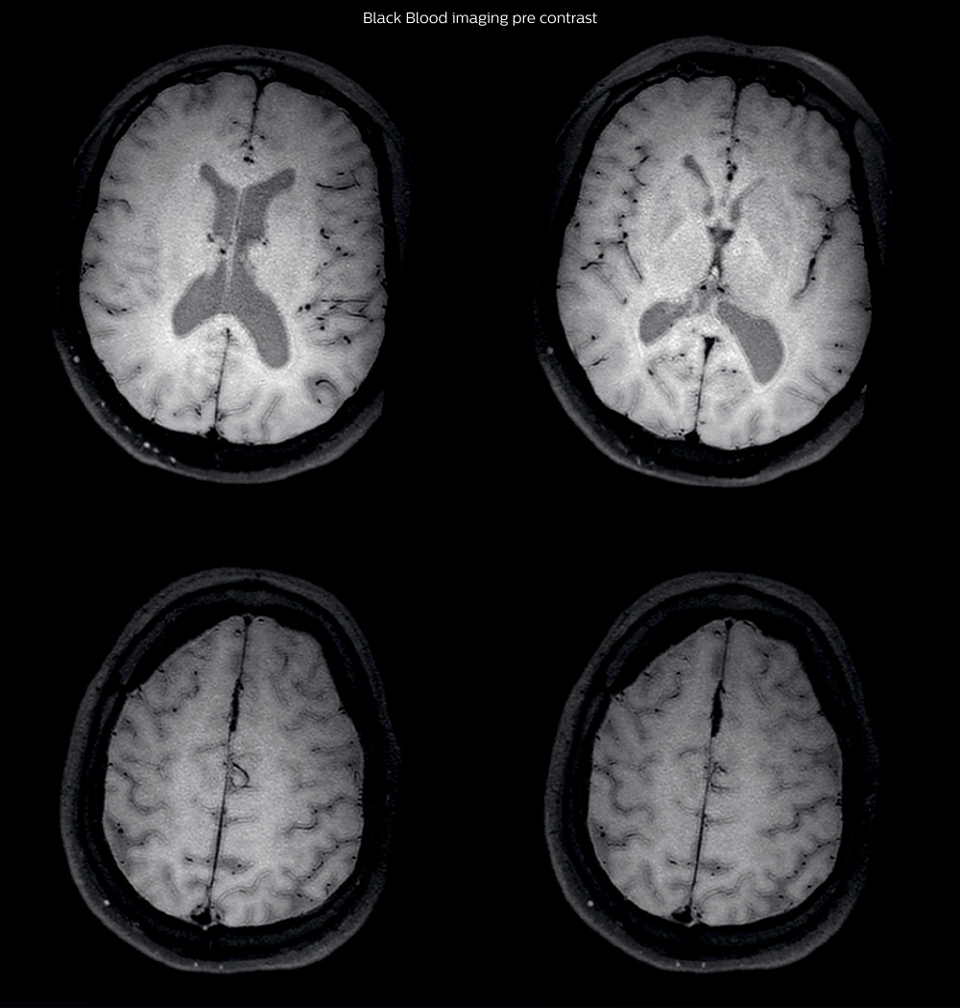

Black Blood Imaging Case 1 B Pre contrast1

On the routine MR sequences that we did, we could see acute

ischemic lesions. We see them very well on the diffusion images,

where acute ischemic lesions usually appear with high signal

intensity and restricted diffusion. However, the etiology of these

lesions cannot be derived from these images.

So, we decided to perform Black Blood imaging. The presence

and the pattern of vessel wall enhancement on Black Blood

imaging, can help us to determine the etiology of the lesion.

Many studies have shown that Black Blood imaging can help

differentiate vasculitis from other causes of vasculopathy, such as

atherosclerosis, with a high specificity [1-3]. In an atherosclerotic

lesion, vessel wall thickening and enhancement are usually eccentric,

while in vasculitis the wall thickening and enhancement are usually

concentric, homogenous, and in a long portion of the vessel.